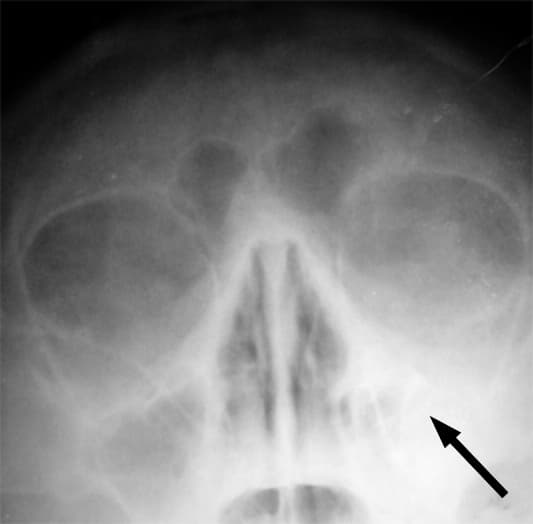

Une sinusite est une inflammation d'un des quatre types de sinus (maxillaire, frontal, sphénoïdal ou ethmoïdal) que comporte le corps humain. On parle de pansinusite lorsque plusieurs de ces quatre types de sinus sont atteints. Les complications sérieuses sont rares. Les symptômes les plus communs incluent : irritation nasale voire congestion au niveau d'une ou des deux fosses nasales, avec douleurs faciales. D'autres signes peuvent inclure : fièvre, céphalée, diminution du sens de l'odorat, larmoiements, maux de gorge et toux, aussi des mauvaises odeurs (dues au pus et à d'éventuels saignements ou à une mycose) et parfois une dysgueusie. Les symptômes peuvent empirer la nuit. On distingue la rhinosinusite aiguë (ou RSA, si elle excède quatre semaines) et la rhinosinusite chronique (RSC) si elle excède 12 semaines. Cette dernière est subdivisée en trois groupes : 1) RSC avec polypes nasaux, présents chez 20 % des patients atteints de RSC ; 2) RSC sans polypes nasaux et 3) rhinosinusite fongique allergique. Lorsqu'un virus, un champignon (mycose), une bactérie ou une allergie affecte les muqueuses du nez, celles-ci réagissent en s'enflammant et en enflant, provoquant l'obstruction des sinus. Dès lors, le mucus n'est plus drainé normalement, et les virus ou bactéries peuvent se développer rapidement. Les sinusites commencent donc, dans la plupart des cas, par une rhinopharyngite virale qui entraîne une altération des capacités épuratoires de l'appareil cilié naso-sinusien et peuvent évoluer vers une authentique sinusite bactérienne. Les sensations de pression que peut ressentir le malade sont dues à la surpression provoquée par l'obstruction des sinus. Les principaux virus en cause incluent rhinovirus, myxovirus, et adénovirus. Les principales bactéries responsables de surinfections sinusiennes incluent Haemophilus influenzae, Streptococcus pneumoniae, Moraxella catarrhalis, Staphylococcus aureus et Anaérobies (rare, lié à un foyer dentaire). Des champignons comme Aspergillus peuvent aussi être en cause ; on parle alors de Sinusite aspergillaire, dont une forme est « pseudotumorale ».